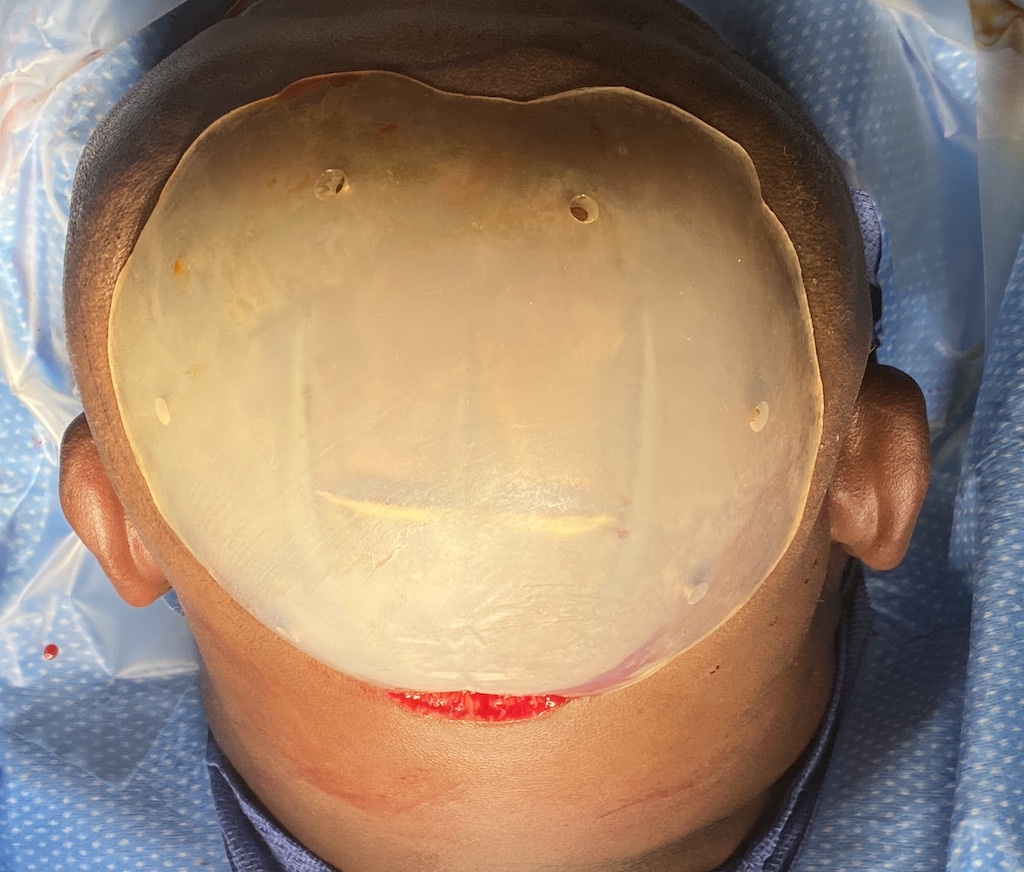

Patient 129

Desire for reduced width/convexity on the sides of his head.

Head narrowing using a temporal muscle transposition technique seen one day postop. He also had an concurrent occipital skull reduction done hence the tape over his incision.

Desire for reduced width/convexity on the sides of his head.

Head narrowing using a temporal muscle transposition technique seen one day postop. He also had an concurrent occipital skull reduction done hence the tape over his incision.